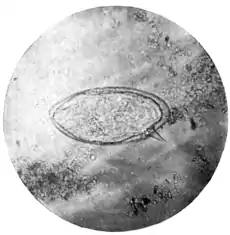

The ovum.—On microscopical examination the uterus of the female bilharzia is found to be stuffed with ova of a peculiar and characteristic shape. They are oval, each egg on an average measuring about 0·16 mm. in length by 0·06 mm. in breadth, and one end of the ovum is provided with a short, stout, and very definite spine. (Plate XIII., Fig. 1.)

| Fig. 1.—Terminal-spined egg of Schistosomum hæmatobium. (Microphotograph: Dr. Bell.) |

The exact nature of the process by which the ova leave the body of the human host has not been satisfactorily explained. Apparently the female worm migrates from time to time from the larger veins to their smaller radicles, and in these deposits her ova. The walls of the bladder are the favourite situations for this purpose. Afterwards the eggs are somehow carried, possibly aided by the spine with which they are provided, towards the surface of the mucous membrane, and then, falling into the bladder, are voided with the urine, a certain amount of blood escaping at the same time.